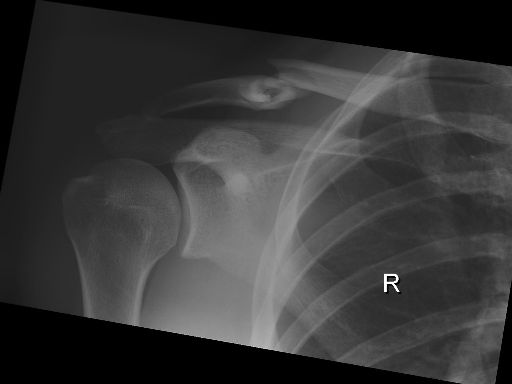

Clavicula-Fraktur (23./25. Juli/2. August 2007)